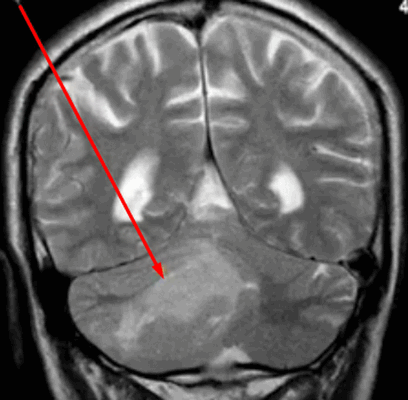

Опухоль мозжечка на МРТ (указана стрелкой)

Опухоли головного мозга долгое время диагностировали исключительно по клиническим признакам, часто слишком поздно. С появлением нейровизуализационных методов стало возможным выявление опасных патологий на ранних этапах их развития. Уже на первых стадиях формирования опухоль головного мозга на МРТ отчетливо видна, а врачи могут планировать дальнейшие действия. Ранняя диагностика увеличивает шансы на выздоровление даже при онкологических заболеваниях.